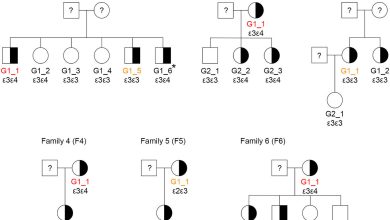

Os cientistas revelam impactos críticos de um fator de risco genético chinês na doença de Alzheimer

Gráfico de pedigree das seis famílias (na coorte da variante genética) com portadores variantes Trem2 H157Y. A cor corresponde ao…